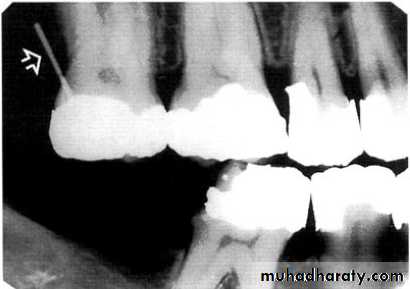

its either pointed or irregular radiopaque projection extending from the proximal root surface.

Calculus may be seen as a ring-like radiopacity encircling the cervical portion of the tooth.

Detection of Periodontal Disease

CALCULUS